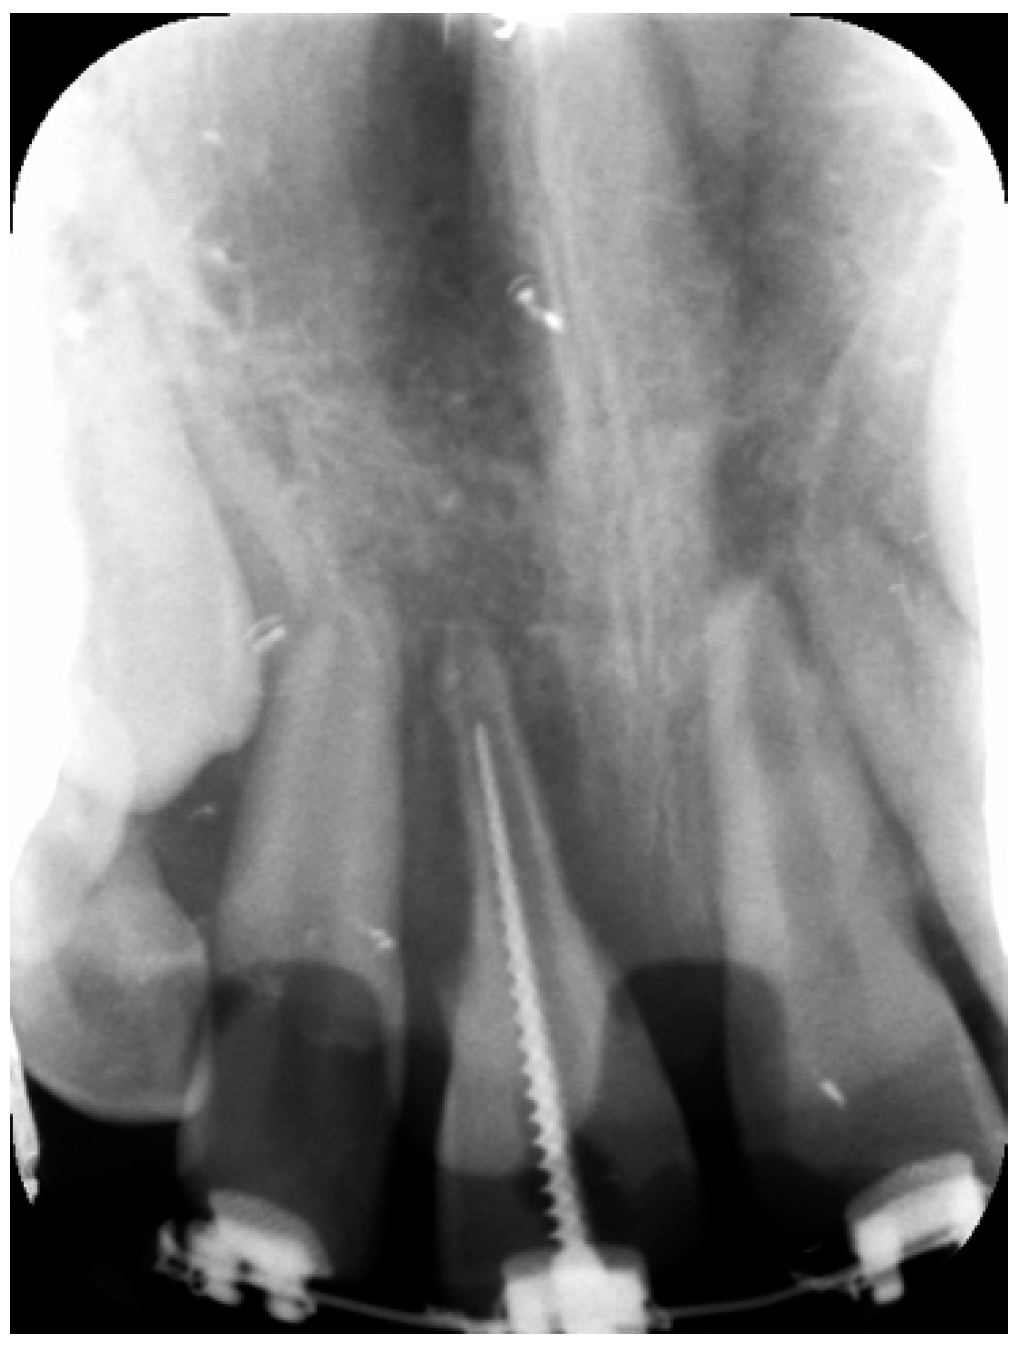

External Root Resorption Management of an Avulsed and Reimplanted Central Incisor: A Case Report

2. Case Report